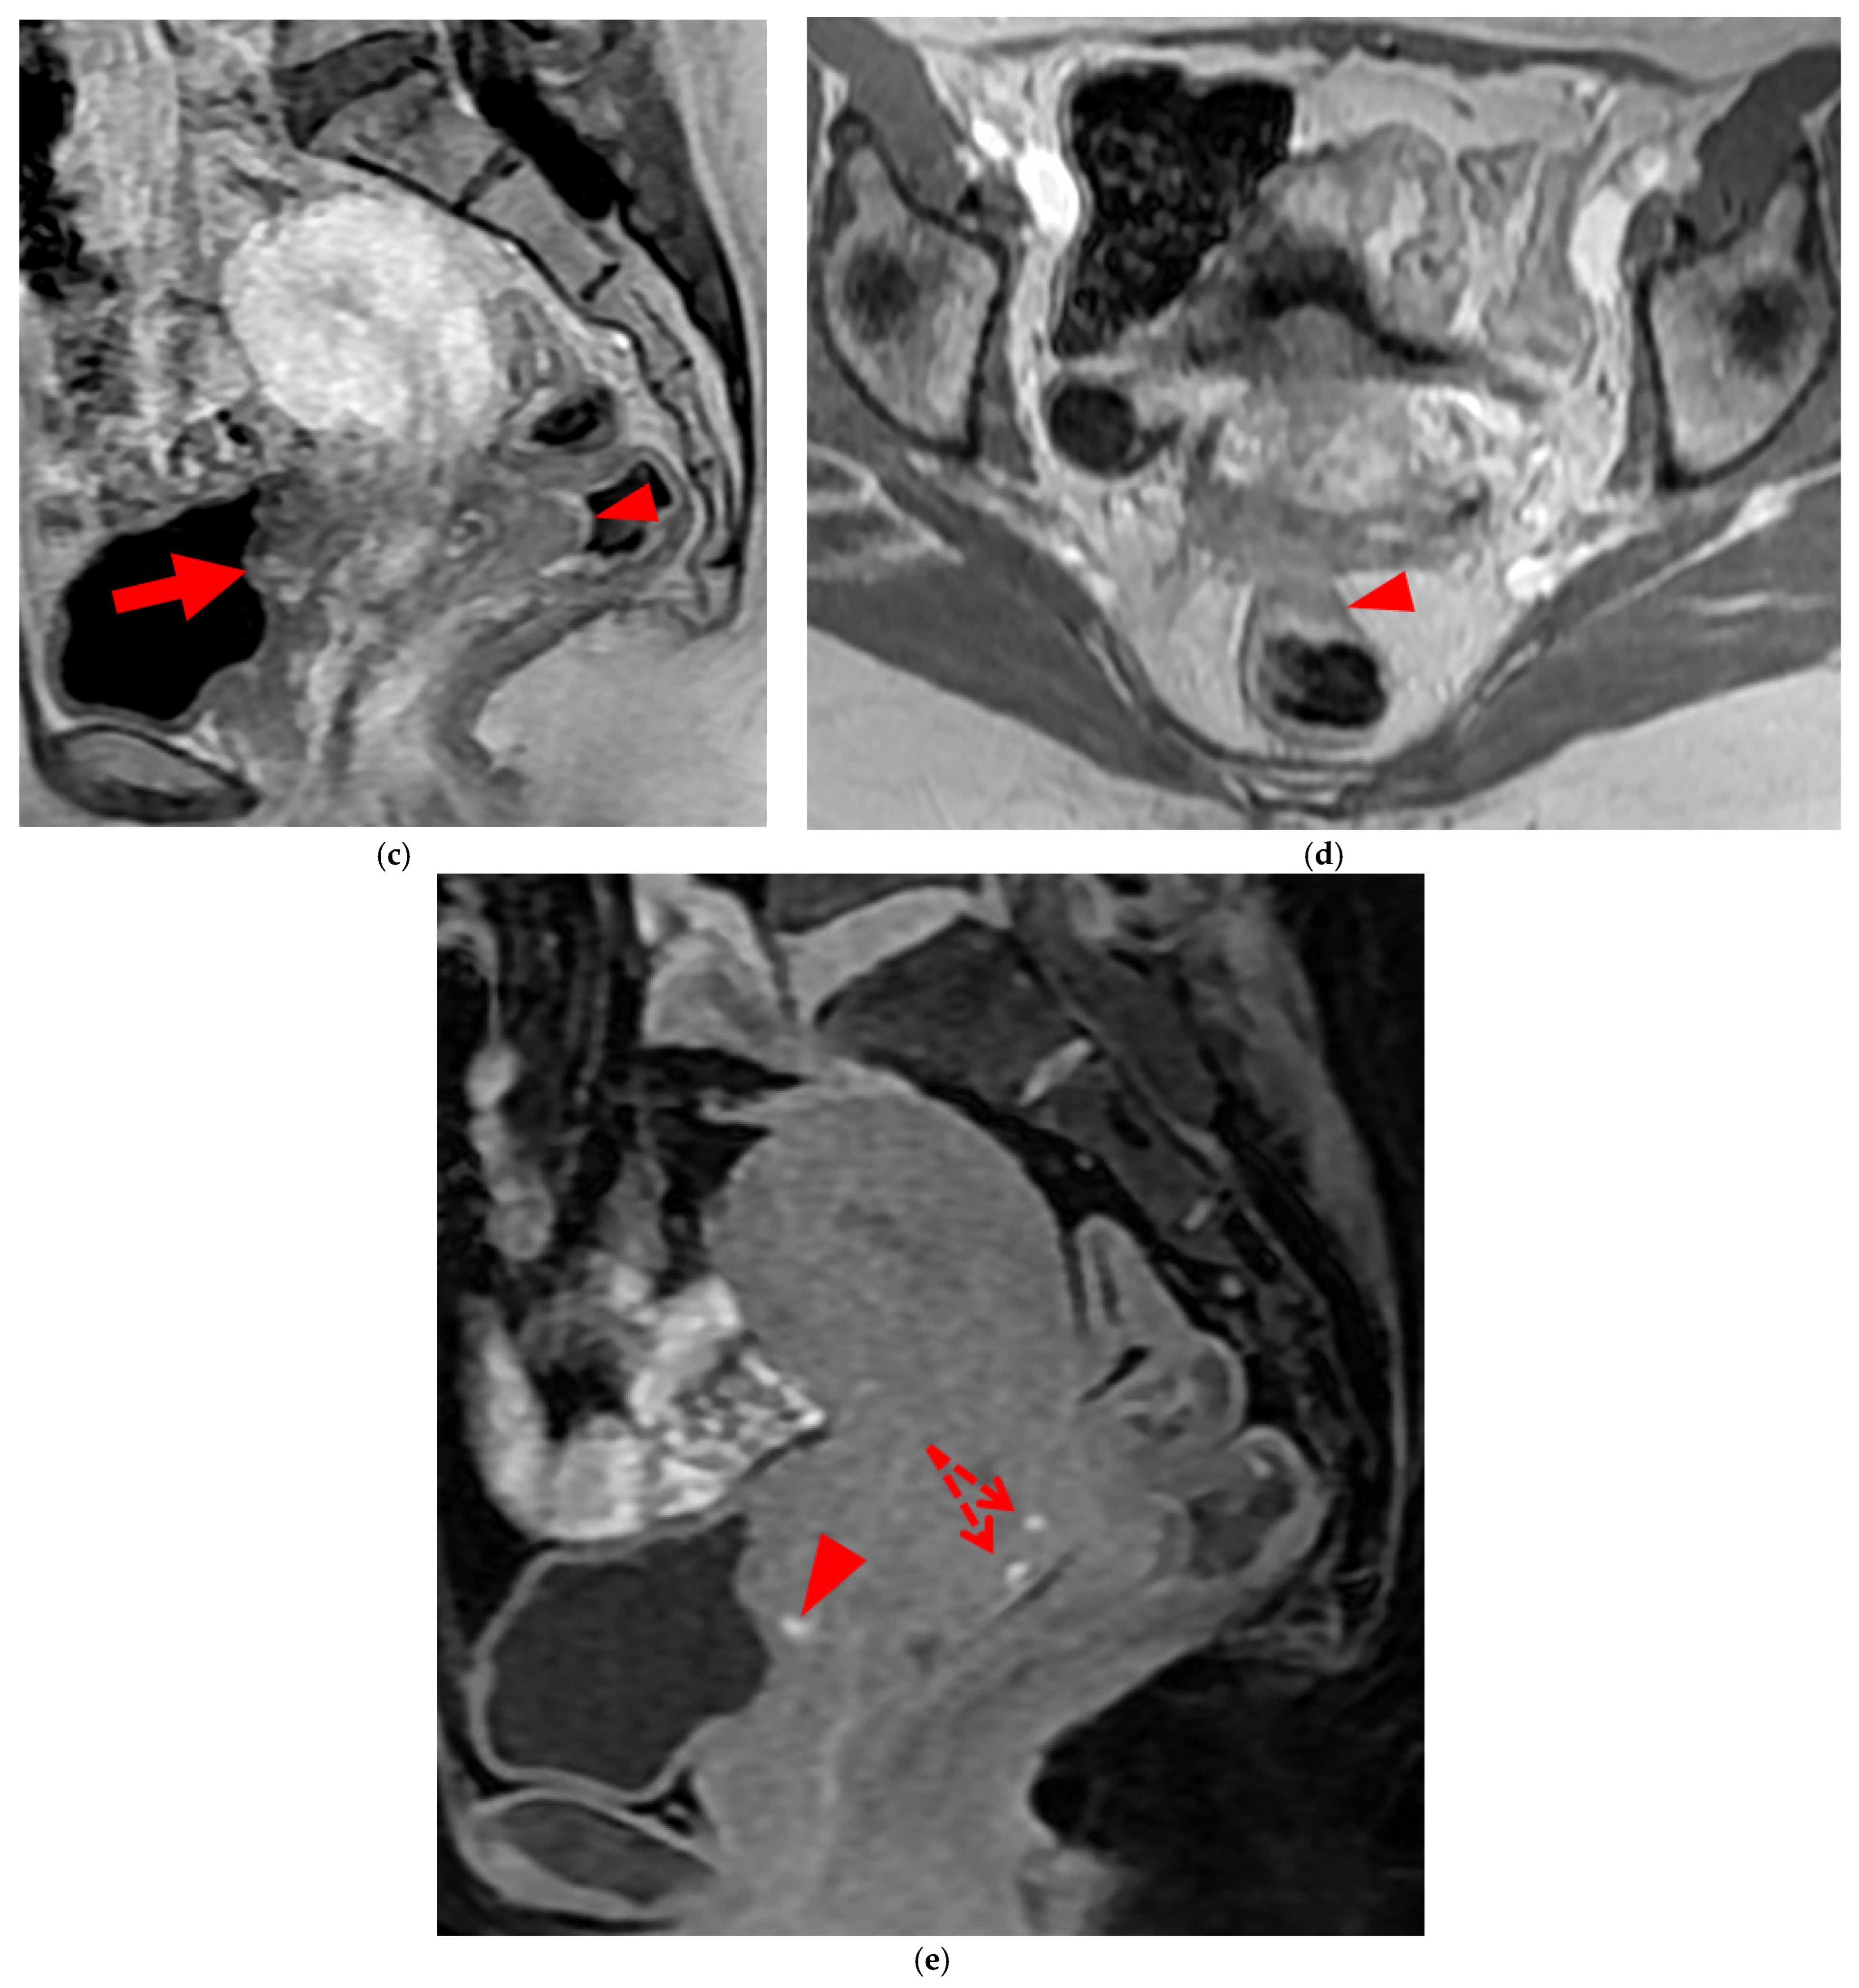

Figure 8. Pelvic MRI scan of a patient with HTD type 6 USLs. (a) Axial T2WI shows a thick (3 mm) right USL (arrowhead) with regular margins, initially classified as a type 3A USL; the left USL is not visible (type 1). (b,c) Coronal (b) and sagittal (c) T2WI show sigmoid colon wall infiltration appearing as a “medallion-shaped” lesion (arrows). The presence of “visceral” involvement of the digestive tract leads to the reclassification of these USLs as type 6.

Figure 9. Pelvic MRI scan of a patient with HTD type 6 USLs. (ad) Sagittal (a) and axial (b) T2WI, sagittal (c) and axial (d) contrast-enhanced T1WI demonstrate involvement of the posterior bladder wall (arrows) and rectal wall infiltration appearing as a “medallion-shaped” lesion (arrowheads). (e) Sagittal fat-suppressed T1WI shows two hyperintense hemorrhagic spots at the origin of the USLs (dashed arrows) and another within the bladder lesion (arrowhead). The presence of “visceral” involvement of both the digestive and urinary tracts results in reclassifying these type 4 USLs as type 6.

A type 6 USL is associated with adjacent pelvic “visceral” involvement in a broad sense. It most commonly affects the digestive tract (Figure 8 and Figure 9), with the rectum and rectosigmoid junction wall thickening: in this case, the lesion often appears as a “medallion-shaped” protrusion into the lumen. Less frequently, the urinary tract is affected (Figure 9 and Figure 10), involving the muscular layer of the bladder or even the distal ureter at the level of the common iliac artery, with stenosis potentially leading to upstream hydronephrosis. More rarely, as USLs are also close to nearby pelvic nerve structures (Figure 11), contiguous involvement of the inferior hypogastric plexus located in the sacro-recto-genital septum (a.k.a. Delbet sagittal fascia) beneath the distal two-thirds of the USL, or exceptional involvement of the sciatic nerve adjacent to the pelvic wall, is possible (Figure 12, Figure 13 and Figure 14).